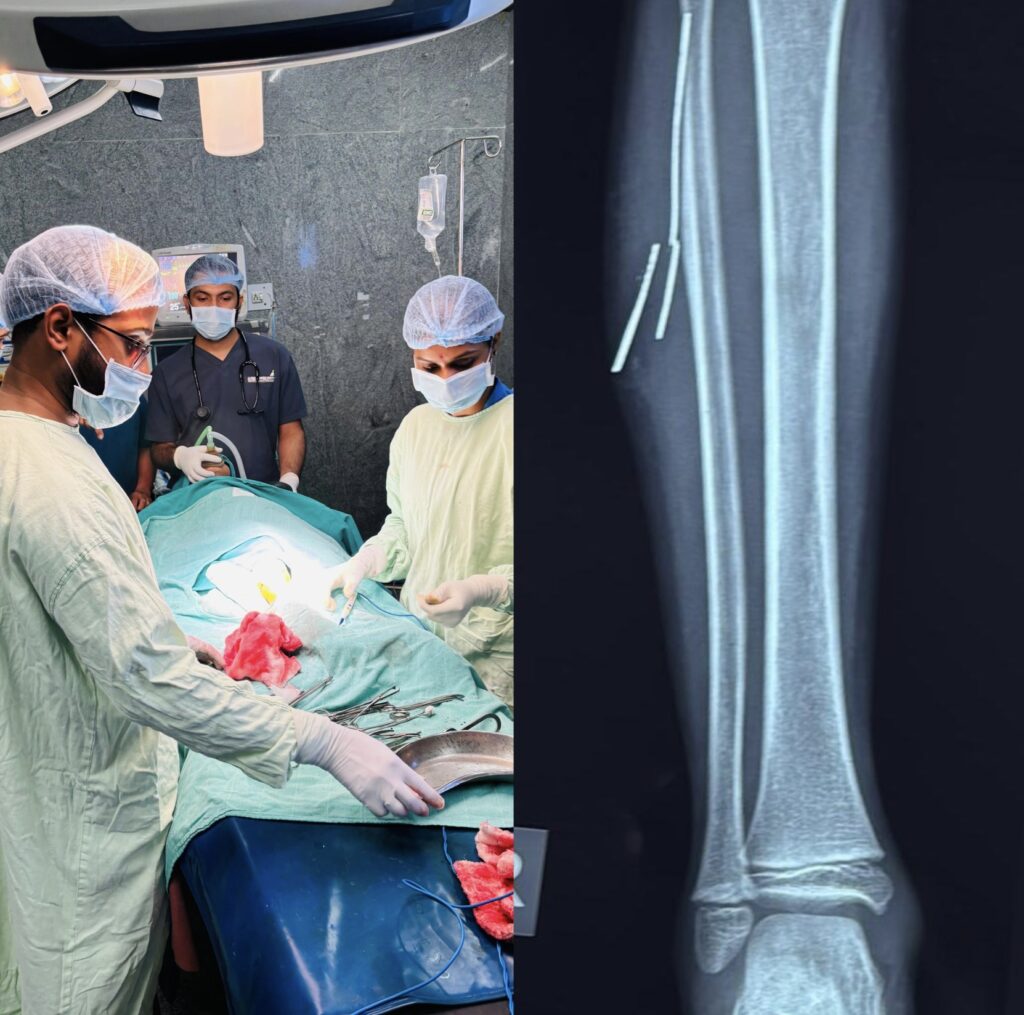

टीमवर्क की ताकत रेडियोलॉजी और सर्जरी विभाग के इस तालमेल की बदौलत सर्जन डॉ. ओ.पी. राज और डॉ. बी.डी. तिवारी ने न्यूनतम चीरफाड़ के साथ सभी चारों तार सफलतापूर्वक निकाल दिए। ऑपरेशन के दौरान एनेस्थीसिया विभागाध्यक्ष डॉ. मधुमिता मूर्ति, डॉ. भावना रायजादा, डॉ. मयंक अग्रे, डॉ. श्वेता कुजूर और डॉ. मिल्टन ने भी महत्वपूर्ण भूमिका निभाई।